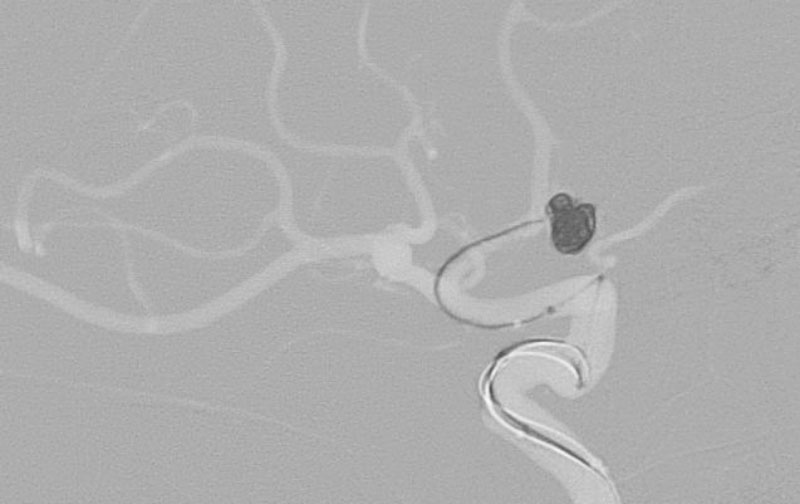

くも膜下出血

左中大脳動脈瘤破裂

40代

救急外来

No.1596 手術後